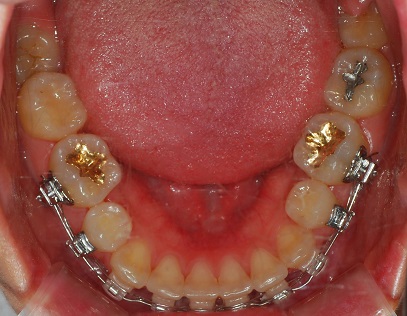

하악 사진